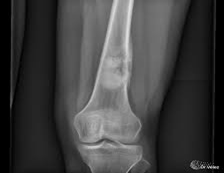

1. Rayos X

Se usa una amplia gama de técnicas de adquisición de imágenes para poder ver dentro del cuerpo y determinar el alcance de un sarcoma óseo y establecer la presencia o ausencia de enfermedad metastásica distante.

Los tumores óseos suelen aparecer en zonas de hueso que crecen rápidamente (Metáfisis). Podemos clasificarlos en diferentes subtipos:

Los sarcomas óseos son poco frecuentes representando hasta el 1% de los tumores malignos. El osteosarcoma es el tipo más común frecuente de tumor primario con 2-3 nuevos casos por millón de persona cada año. La mayoría de las veces afecta a personas jóvenes de entre 10 y 30 años de edad